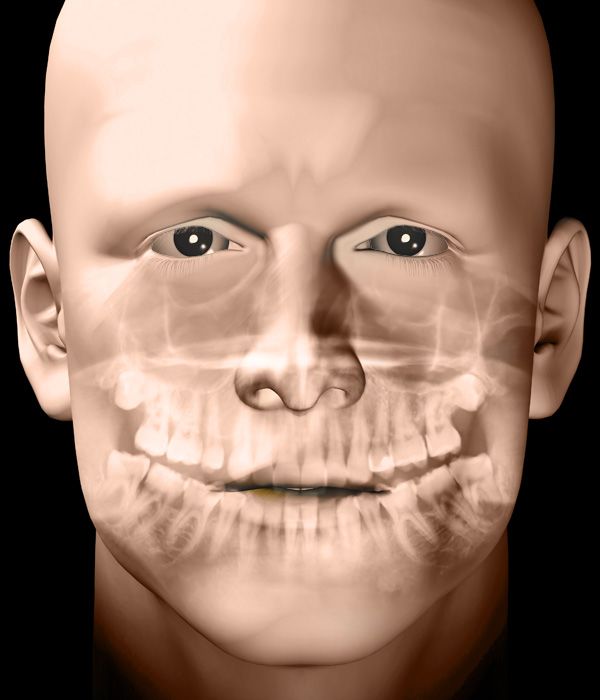

Advanced Oral Surgery from Compassionate Experts

Dr. Sean Healy and Dr. Diego Hurtado use advanced techniques to minimize discomfort and healing time after wisdom tooth removal. Sedation can ensure your comfort and platelet-rich fibrin, containing growth factors, naturally stimulates the healing process. At a follow-up appointment, one of our surgeons will monitor your recovery.

If you require an extraction, our surgeons will use gentle techniques to remove your damaged tooth and preserve the surrounding bone structure. Our sedation options can also keep you comfortable and relaxed during the procedure. Often, we can combine extractions with same-day dental implants.

Dr. Healy and Dr. Hurtado offer several types of implants including traditional and same-day implants, as well as the All-on-4® method. We are one of the few practices in New Mexico to use a state-of-the-art live navigation surgery system for more accurate implant placement.

During bone grafting, our surgeons will replace lost tissue and rebuild your jaw structure. We will typically use a sample of your own bone, taken from your hard palate or another part of your body, or a synthetic material. The new tissue will strengthen the jaw, forming a solid base for implants.

Sinus lifts are similar to bone grafting, and our surgeons may recommend this treatment if you have lost bone volume on your upper jaw. This option will restore lost tissue and also reposition your sinus membranes. In some cases, our surgeons can eliminate the need for a sinus lift by placing zygomatic implants.

In some cases, your general dentist or physician may refer you to us for a biopsy. Dr. Healy or Dr. Hurtado will take a small tissue sample, numbing your mouth so that the procedure involves minimal discomfort. Then he will send the sample to a lab, where they will test for cancer and other oral health concerns.

Following an auto accident, sports injury, or other incident and initial emergency treatment, Dr. Healy and Dr. Hurtado can restore your appearance, oral function, and oral health. Using advanced imaging technology, such as cone beam scans, he will determine the right treatment option for you.